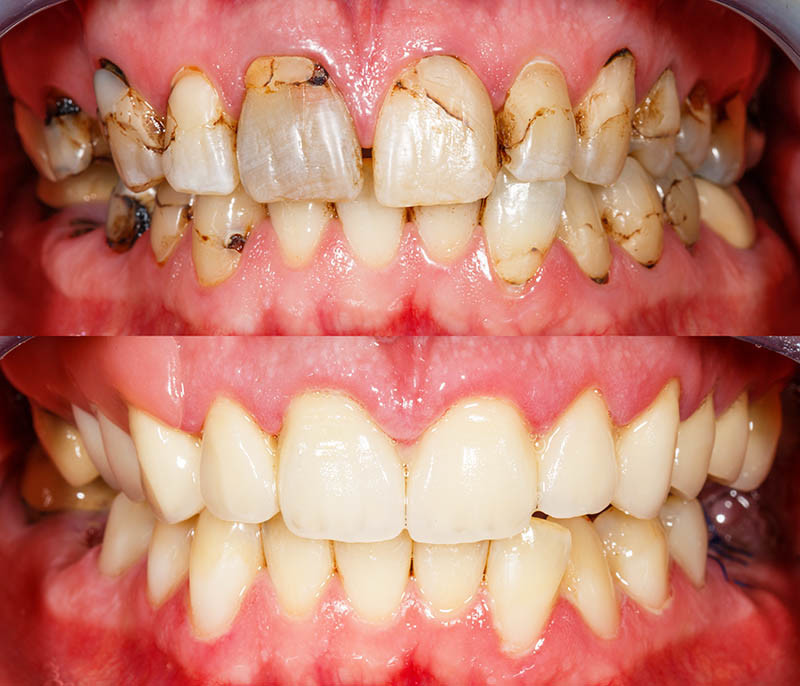

What causes rotten teeth, Symptoms and Treatment Options

Rotten teeth happens when you don’t detect the cavity and a sever tooth decay happens. There is more to your teeth than just a spectacular smile. If you are suffering from a serious form of tooth decay known as Rotten Tooth, you can experience more than just a toothache. Your overall health can be affected. If you have bad teeth, there are a number of options for saving a rotting tooth.

What Happens to a Rotten Tooth?

A rotten tooth is one that is severely decayed. The decay, also known as dental caries or a tooth cavity, begins with the breakdown of the tooth enamel. Plaque builds up and combines with bacteria to break down the enamel. Once the enamel has broken down, cavities develop. If you fail to treat your cavities, they will get worse. Dental caries is an open invitation to bacteria to further invade your teeth and beyond.

Dental caries does not discriminate. A tooth cavity can happen at any age. Baby bottle tooth decay is a breakdown of enamel caused by the sugar found in formula and extensive use of a baby bottle. The formula will pool around the teeth and combine with bacteria which accelerates breakdown in enamel. The condition is most common with a rotten back tooth or rotten bottom teeth. Thanks to a variety of available treatments, we can restore even those teeth you may believe to be permanently damaged.

What Causes Rotten Teeth?

Dental caries results from a combination of not taking care of your teeth, the foods you eat, and in some cases, drugs of abuse or even legally prescribed medications. Foods that are high in sugar or starch are known to aid in breaking down tooth enamel. If you consume a lot of sugary drinks, the deterioration of enamel is accelerated. The presence of naturally occurring bacteria also accelerates this process. The bacteria and food build up and cause an acid that attacks the enamel accelerating the breakdown.

Practicing good oral hygiene can slow the process of enamel deterioration and tooth decay. Brushing and flossing away the food following every meal takes away its opportunity to attack and break down your tooth enamel.

How do you know if you have a rotten tooth?

The first symptoms most people notice are sensitivity to hot and cold food and drinks. Sugary and sweets can cause similar sensitivity. You may feel pain when you bite into your food. When the level of decay progresses, toothaches become not only a regular event but more severe as time goes on. Bad breath that does not go away and having an unpleasant taste in your mouth are other common symptoms. You may experience swelling in the gums and in your face as the dental caries progress.

Visually, you might first notice discoloration as the enamel deteriorates followed by tiny holes in your teeth. You will also see dark spots as the decay becomes more apparent. As the decay gets worse, the toothaches will become unbearable, your teeth can crack, pieces of your teeth can break off, or a tooth can completely break at the gum line. You will start having trouble eating and may lose weight. It is possible you will lose important nutrients that are critical to your health. The symptoms of a rotten tooth will grow more severe as time goes by. You are more likely to notice this kind of symptom in a rotten back tooth or rotten bottom teeth. In comparison, rotten front teeth are relatively rare.

Tooth Decay Stages

There are three tooth decay stages. Early-stage decay is little more than an initial breakdown in the tooth enamel. There might be very tiny cavities, but early tooth decay stages can usually be reversed. Advanced tooth decay stages show significant cavities. At this stage, dental caries has gone further than just the enamel but have not yet reached the pulp of the tooth. Very advanced tooth decay stages show dental caries in the pulp of the tooth.

Your dentist will decide the level of treatment according to the level of decay. In addition, in most cases your dentists should be able to save the rotten tooth.

What to do for a Rotten Tooth

When putting together your plan for your rotten teeth treatment, your dentist will first consider the location of your tooth and the stage of the decay. They will also consider whether the tooth is a baby tooth or a permanent tooth. Throughout your life, your smile is not only your first impression but also your lasting impression. If your decay is on a front tooth, your dentist will take a different path towards restoration than when your decay is on a molar. No matter where your bad teeth are located, there are several options for saving a rotten tooth.

Decay that occurs on either your back teeth or your bottom teeth is treated with traditional fillings and crowns. It is more common for your back teeth to decay because they are harder to reach and may not get the care that your front teeth do when you brush and floss. No matter what stage of decay, you will notice a difference in your rotted teeth before and after treatment. With several options available, your rotten teeth do not need to be considered permanently damaged. The rotten teeth treatment options for each stage of decay are: